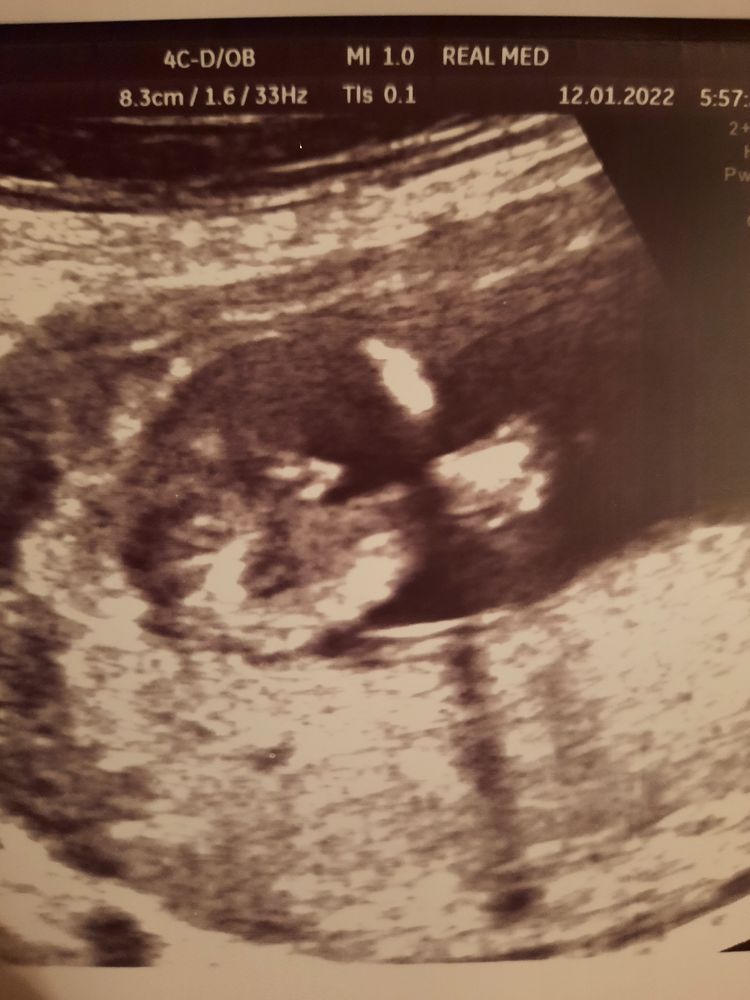

УЗИ 16 нед

Поздравляю с мальчишкой 💙💙💙! Изображение Вот наша фотка , все идентично! ))